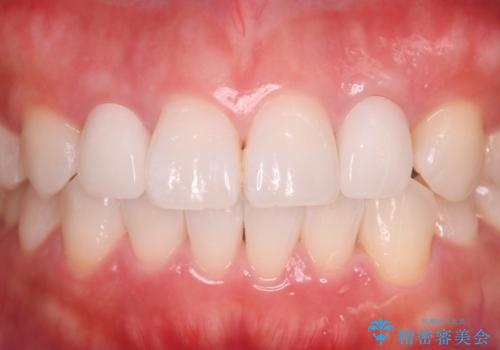

- 食べ物が歯間にはさまることを主訴に来院された患者様です。レントゲンより上顎両側切歯に根管治療が実施されていますが、被せ物が入っておらず、充填物に劣化像もみられました。歯の色の差も気にされていたのでオールセラミッククラウンにて治療いたしました。

より歯の色をきれいに見せたいという希望があったため、ホワイトニングも実施いたしました。食べ物の詰まりも改善し、きれいな仕上がりになったので非常に満足いただけました。